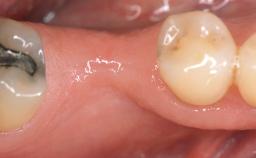

A 30-year-old woman was referred by her general dentist for evaluation of an esthetic complication related to previous implant treatment for congenitally missing maxillary lateral incisors. The patient’s chief complaint was the inadequate esthetic appearance of her smile. The case demonstrates the use of a combined approach to achieve optimal results. Two different flap designs - a tunnel technique and a coronally advanced flap - are employed based on the surgical objectives for the affected site.

Jaw Maxilla

Area Anterior

# of Teeth 2

# of Implants 2